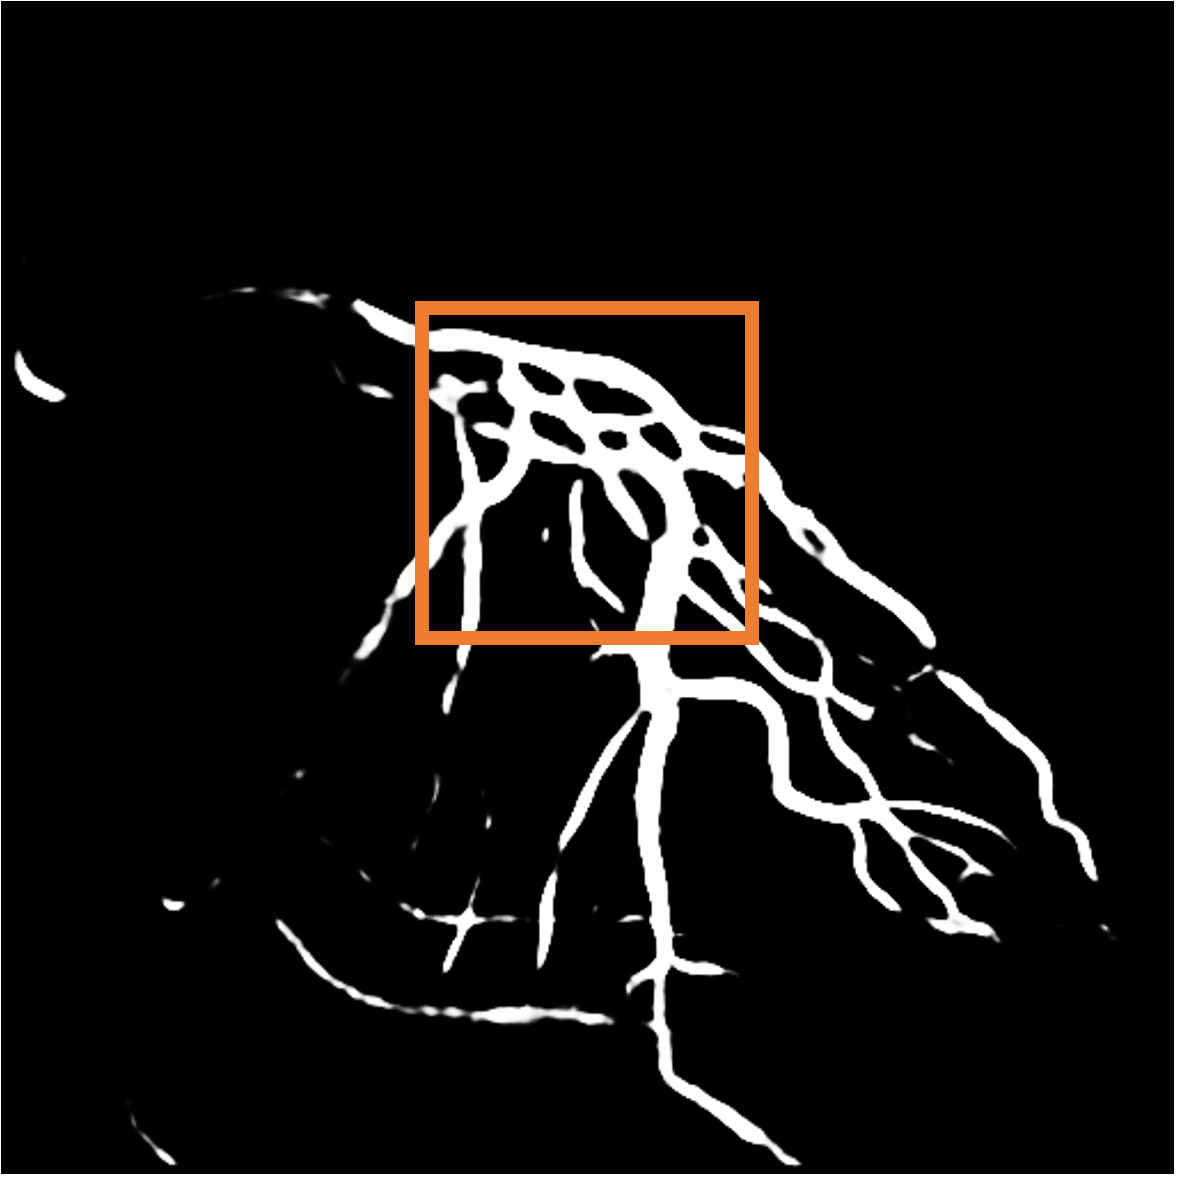

As for the foreground, we observe that the contrast agent flows out from the catheter. Therefore, we consider the Eulerian motion field, as shown in Figure 4, to be a more reasonable specification of blood flow behavior compared to the traditional motion field.

Parallel loss.

Clearly, the direction of blood flow should align with the course of blood vessels (Figure 4). Hence, we design the parallel loss to achieve a parallel alignment between them. Initially, we conduct skeletonization and distance transform on the masks obtained from Section 3.1, and calculate pixel-wise cosine similarity between these transformed masks and the predicted flow:

| (3) |

where represents the value obtained from the distance transform at pixel coordinate , and are the image gradients from the two spatial directions, and denotes the predicted flow value at position .

Layer separation bootstrapping.

To validate the effectiveness of the layer separation bootstrapping, we train foreground and background canonical images using the same representation. The results are shown in Table 2, where optimizing both foreground and background canonical images simultaneously leads to a decrease in the Dice score by 0.0877. The comparison is shown in Figure 9 (a), where the orange area indicates the difference between without and with Layer separation bootstrapping. The bottom-right corner shows a zoom-in patch, highlighting the significant effect of the bootstrapping step.